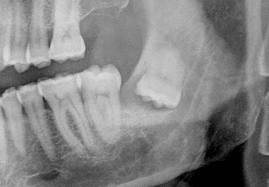

Μια συνηθισμένη επίσκεψη στον οδοντίατρο για να βγάλει τους φρονιμίτες του απέβη μοιραία για τον 18χρονο Benjamin LaMontagne από το Long Island, ο οποίος δύο ημέρες αργότερα «κατέληξε» στην αγκαλιά της μητέρας του, αφού είχε προσβληθεί από μία σπάνια ασθένεια που «κατέφαγε» την σάρκα του!